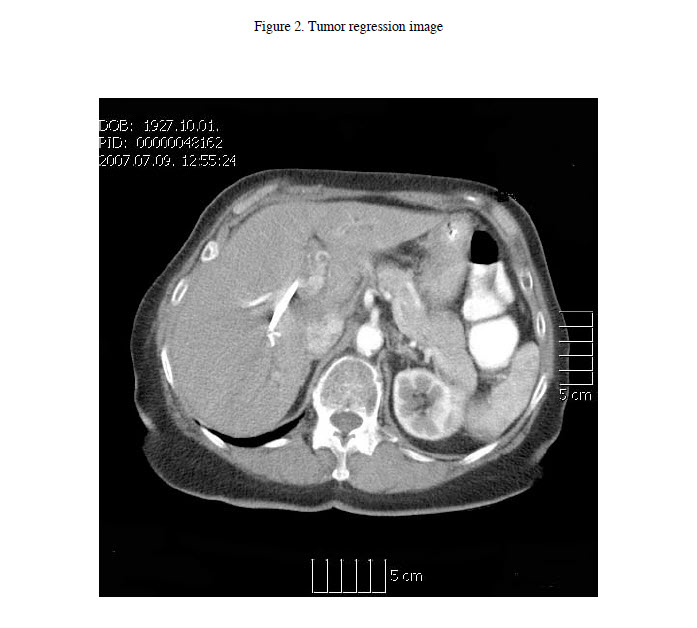

In the beginning of April 2007, the patient began oral administration of the MSQ 15D dietary supplement, 2tbsp TID. In the middle of June 2007, liver function test demonstrated reduced levels of enzymes (AP: 1120 U/l, GGT: 437 U/l, GOT: 49 U/l; GPT: 22 U/l, Total bilirubin: 19 µmol/l). The CA 19-9 marker was 77 U/ml (also see Table 1). An abdominal computed tomography exam was subsequently performed that found no tumor around the porta hepatis (Figure 2).

This study demonstrates the result of our hypothesis in a case of a rapidly lethal cancer, hilar cholangiocarcinoma with an elderly patient. Administration of the MSQ 15D dietary composition led to regression of the tumor as demonstrated by computed tomography scans. The course of the disease is particularly interesting. The elevated liver function markers decreased over the first 5 months of the therapy during which time the tumor also regressed. Subsequent to a urinary tract infection, the markers began to rise. We have earlier found a link between infection and cancer, so it appeared that the infection triggered a reversal of the recovery process. Therefore, we decided to switch over to the more active MSQ 11E composition that contained additional apple cider vinegar, a natural antibiotic.